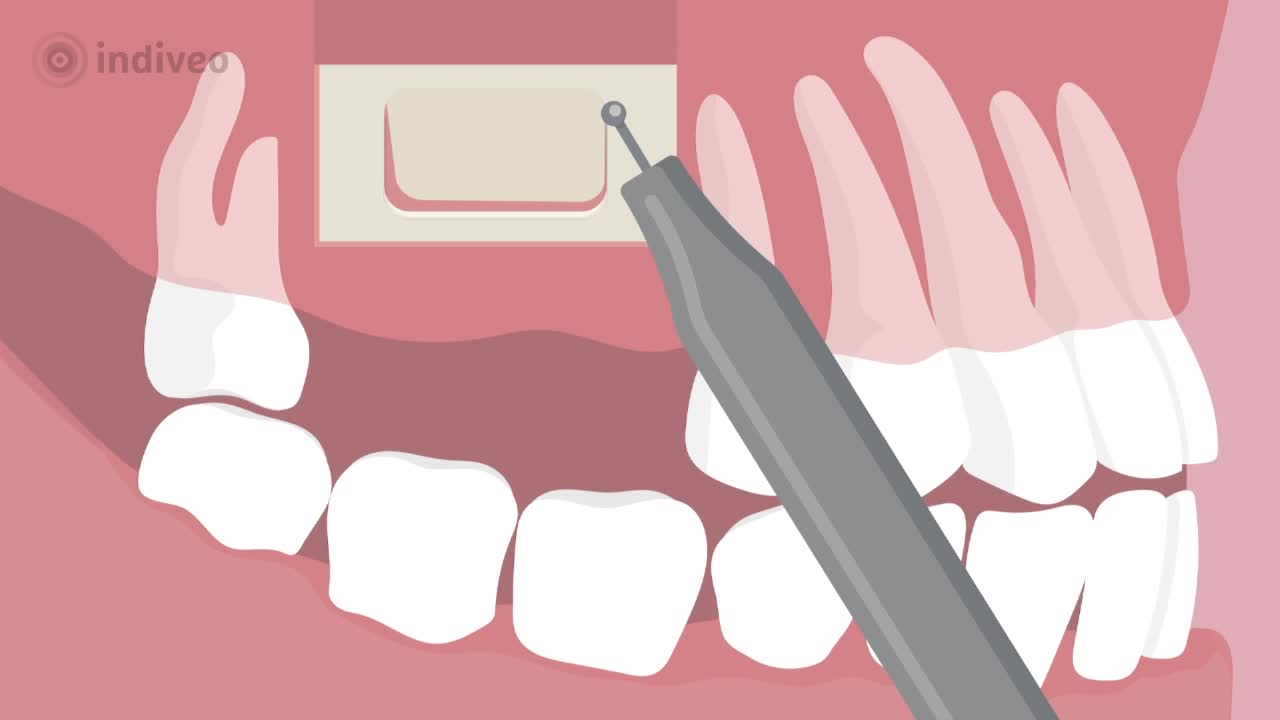

In deze Divi krijgt de patiënt uitleg over een sinusliftoperatie. De patiënt leert waarom er te weinig bot in de bovenkaak is voor een implantaat en hoe dit komt. Ook wordt uitgelegd hoe de operatie verloopt en wat de patiënt kan verwachten voor, tijdens en na de ingreep.

De patiënt wordt geïnformeerd door middel van animatie, illustratie en tekst.